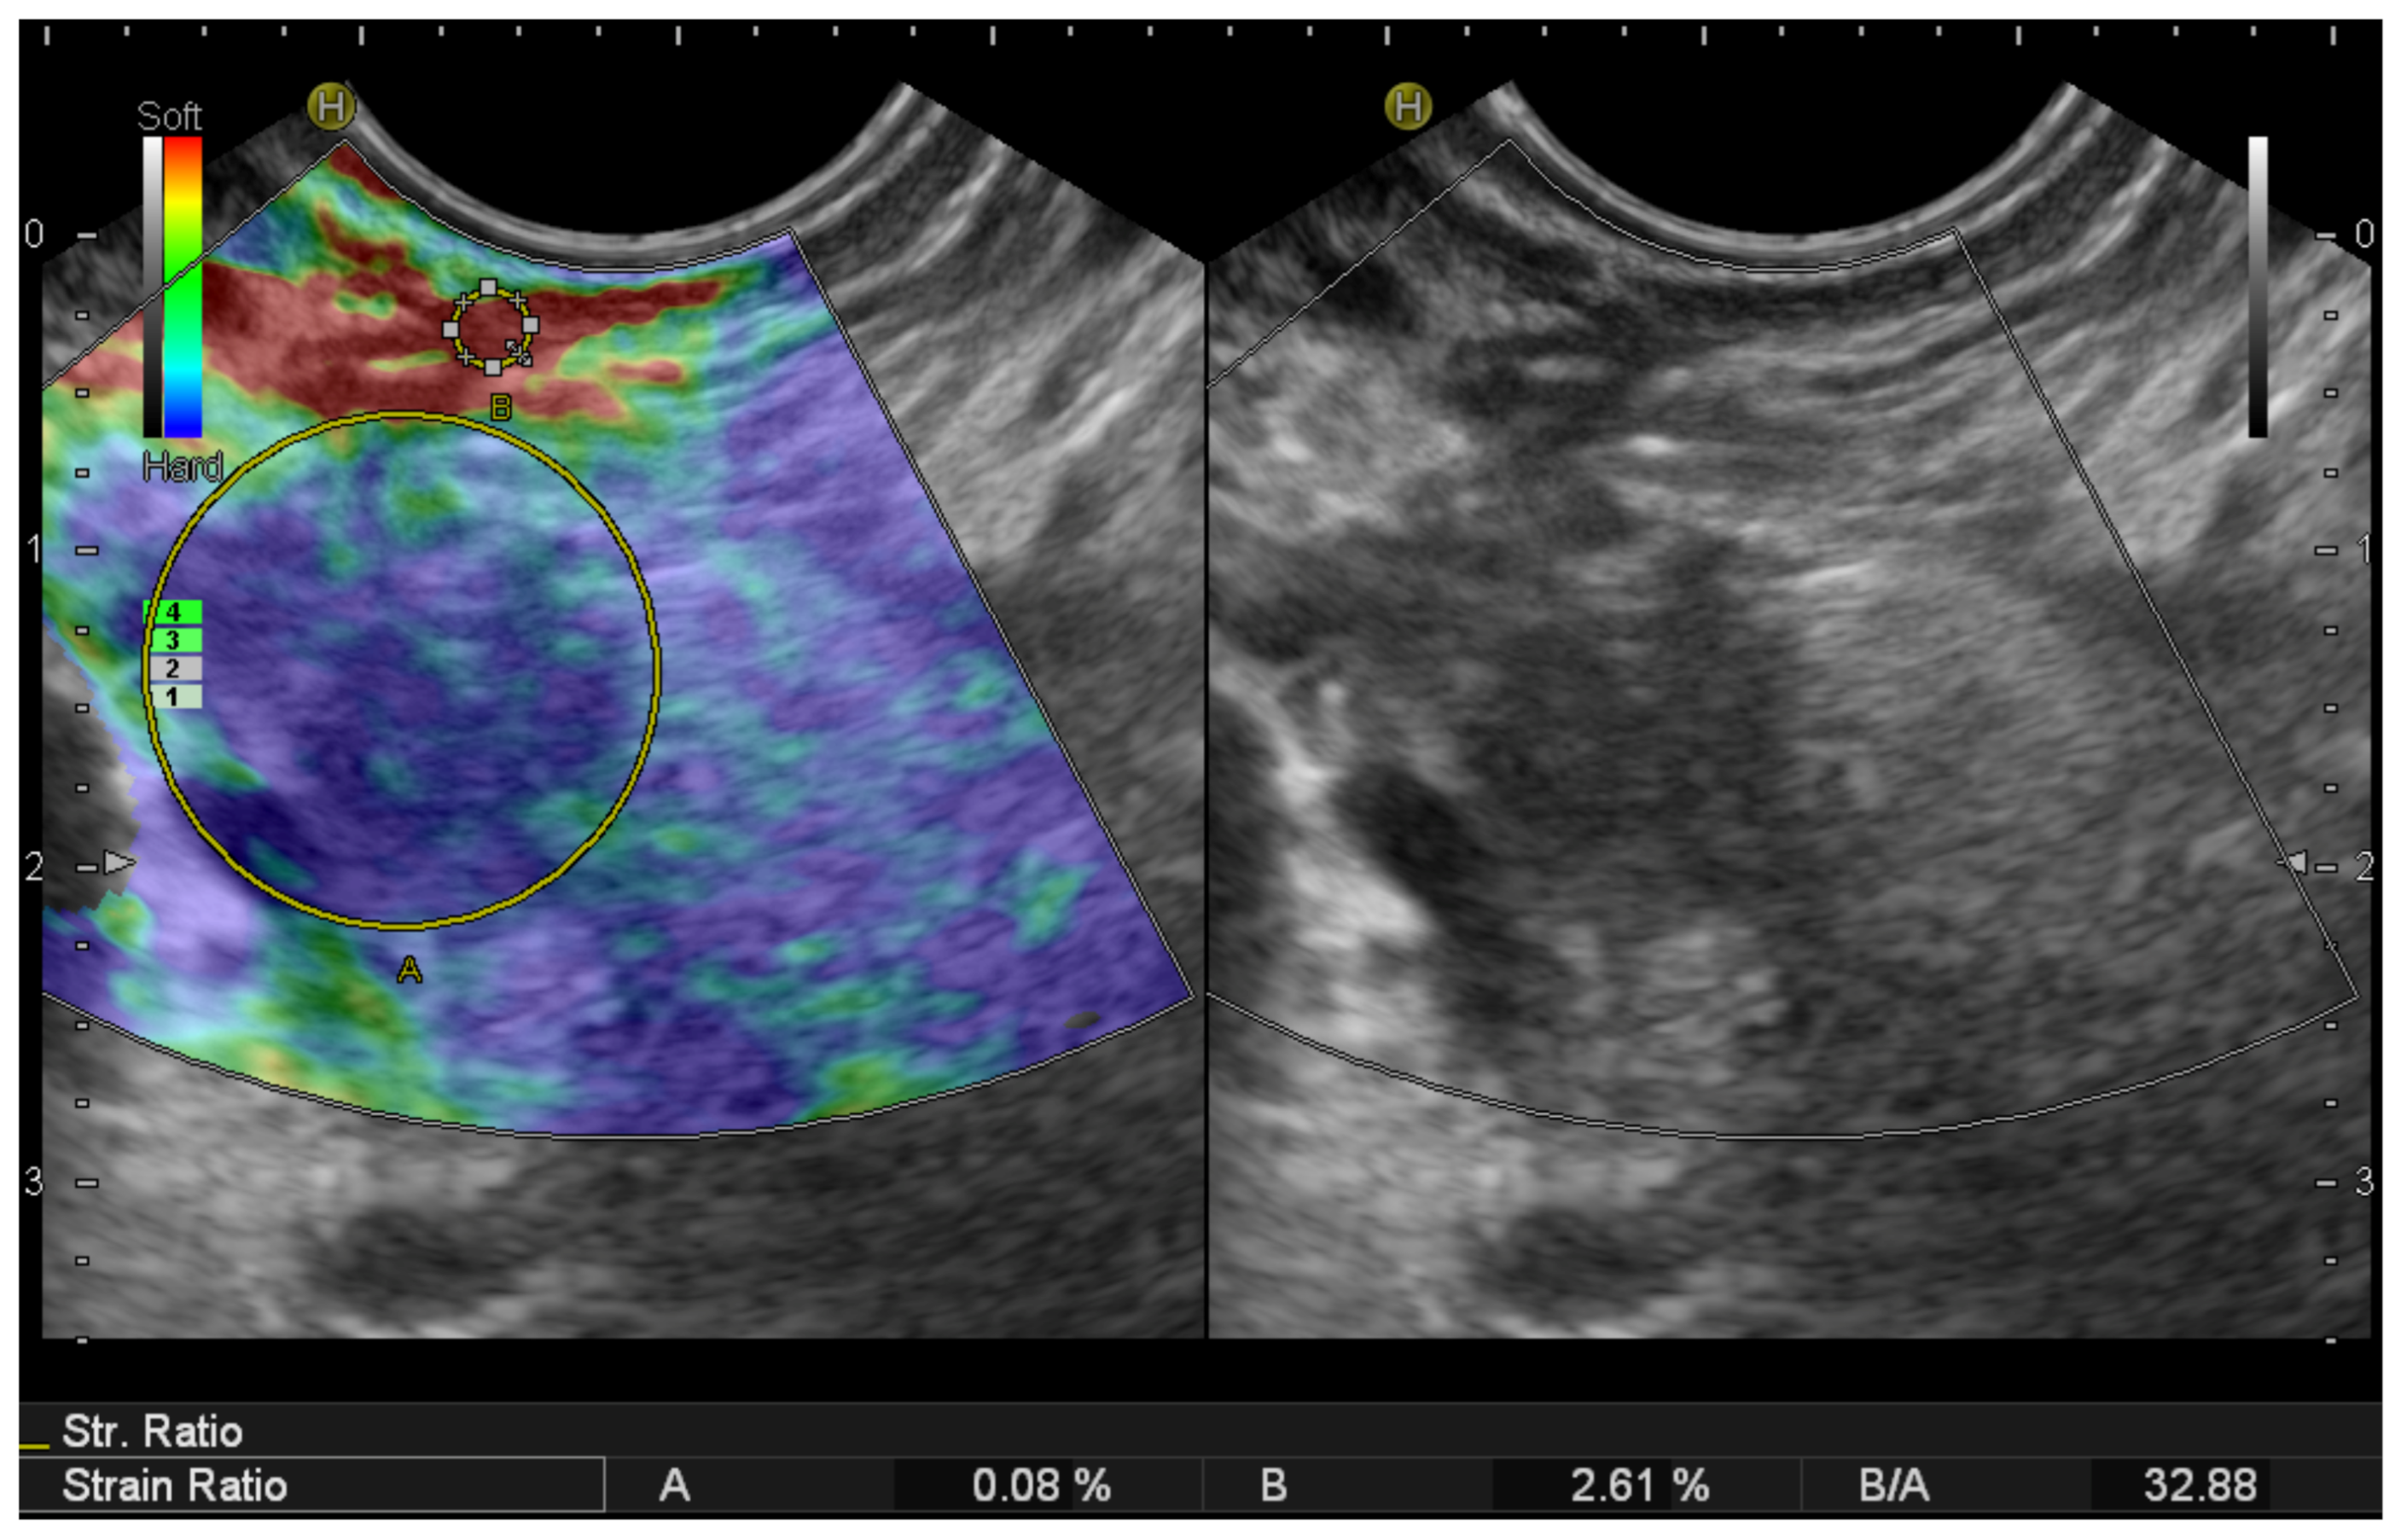

2.2. EUS Elastography

- Carrara, S.; Di Leo, M.; Grizzi, F.; Correale, L.; Rahal, D.; Anderloni, A.; Auriemma, F.; Fugazza, A.; Preatoni, P.; Maselli, R.; et al. EUS elastography (strain ratio) and fractal-based quantitative analysis for the diagnosis of solid pancreatic lesions. Gastrointest. Endosc. 2018, 87, 1464–1473. [Google Scholar] [CrossRef]

- Ignee, A.; Jenssen, C.; Arcidiacono, P.G.; Hocke, M.; Möller, K.; Saftoiu, A.; Will, U.; Fusaroli, P.; Iglesias-Garcia, J.; Ponnudurai, R.; et al. Endoscopic ultrasound elastography of small solid pancreatic lesions: A multicenter study. Endoscopy 2018, 50, 1071–1079. [Google Scholar] [CrossRef]